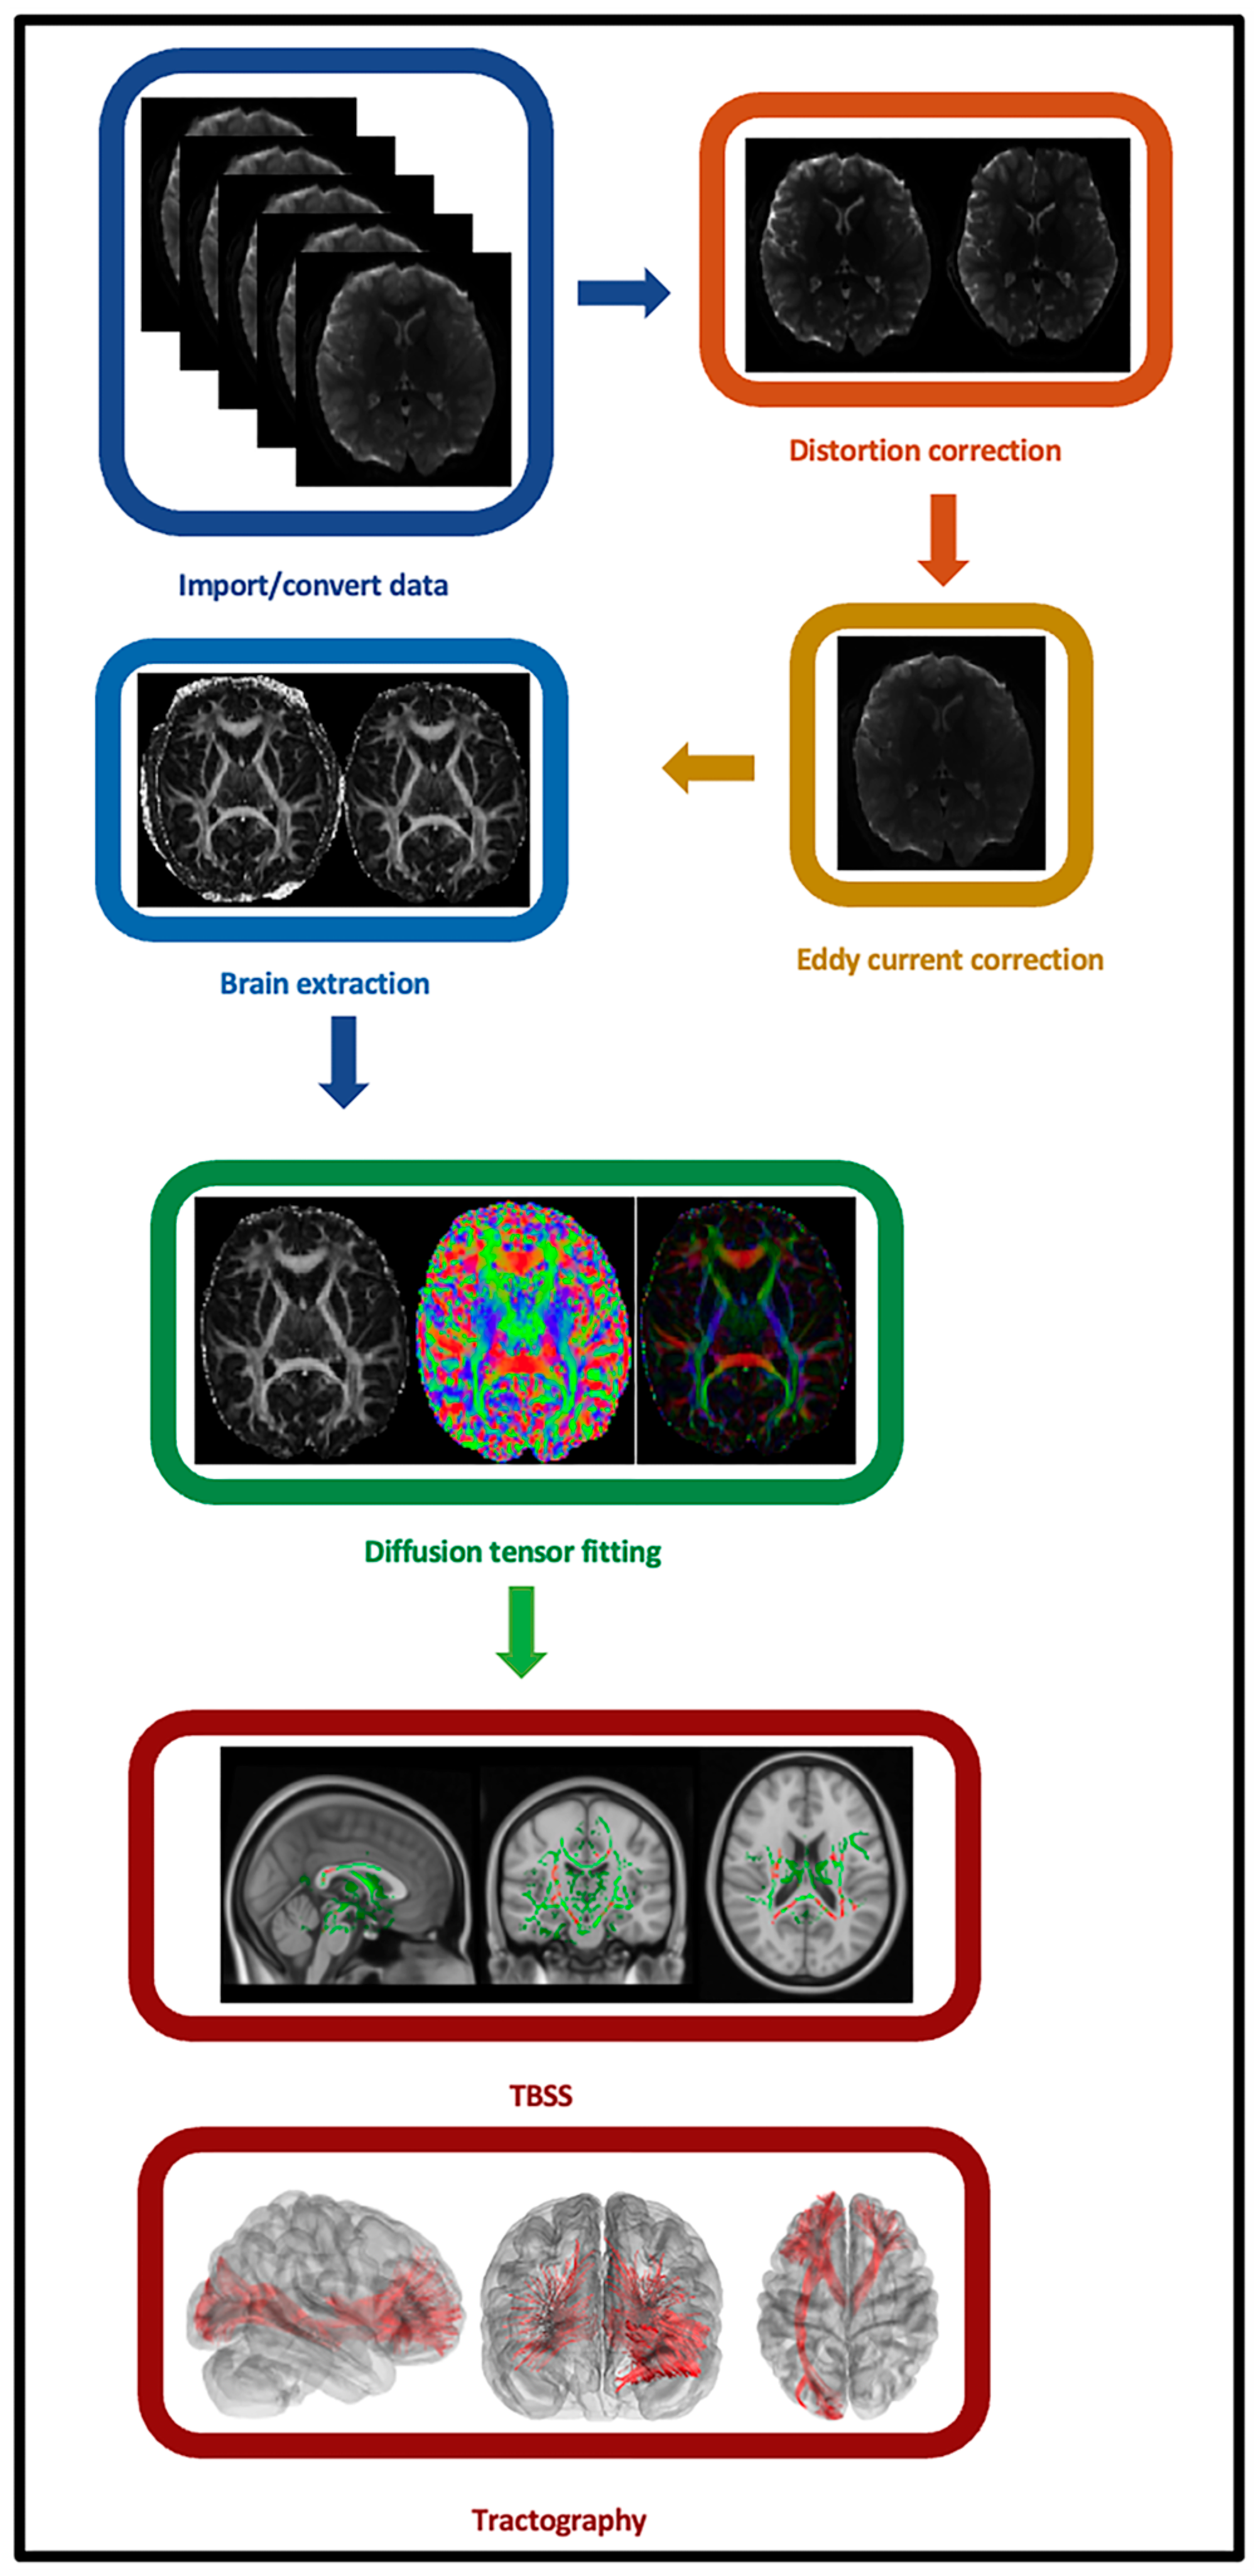

2.5. Individual-Level Imaging Data Preprocessing

2.6. Individual-Level Imaging Data Processing and Analyses

2.7. Secondary Tract-Based Spatial Statistics (TBSS) Analysis